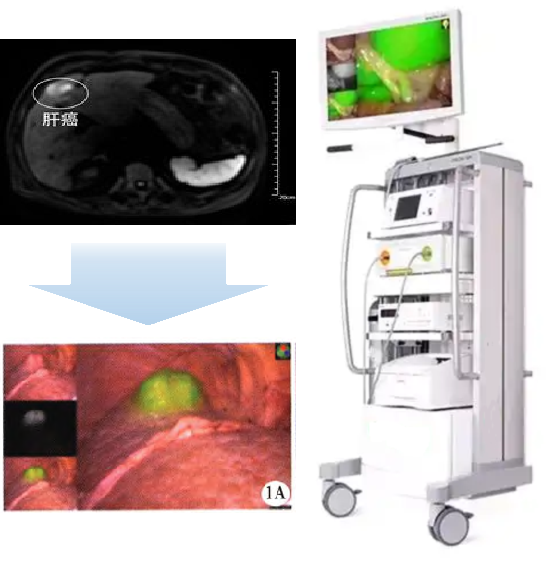

双模态造影剂PL002

PL002是浙江普利药业有限公司研发的荧光/磁共振双模态造影剂,开发荧光/磁共振双模态造影剂成为提高原发性肝癌手术效率的有效方案。双模态造影剂的荧光成像能力可用于肝癌术中荧光导航,而磁共振增强能力可用于在术前判断肝脏代谢能力,推测肿瘤及肝脏对造影剂的摄取情况,提高肿瘤诊断精度,降低术前规划难度。

PL002相较于吲哚菁绿具有明显优势。目前吲哚菁绿在临床使用中存在给药到手术时间不确定的问题,可能造成病灶与正常组织对比度不足,影响术中的病灶的判断,PL002采用独特的钆络合物与荧光分子共价键结合的分子结构设计,这种设计能够让医生在术前通过磁共振成像确定造影剂在病灶中的聚集情况,进而针对患者个体情况来对手术时间进行规划。同时,由于PL002体内更为稳定,在荷瘤小鼠模型中同等条件下荧光成像效果维持时间长于现有荧光造影剂,也保证了其在临床应用中具有更宽的手术窗口。

使用双模态造影剂可以为手术医生提供更加丰富的诊断信息,降低术中的决策压力,避免过度切成,增加发现微小病灶的可能性,最终实现患者的全面获益。此外,相较于传统荧光造影剂,PL002的安全性更高、体内更为稳定,成像效果更佳,为其临床使用提供了有效的支持。